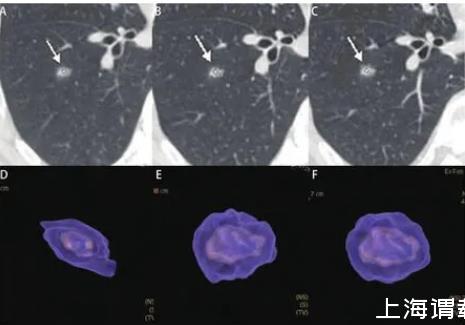

圖6男,56歲,右下葉亞實(shí)性結(jié)節(jié),直徑約為0.9 cm,病理為浸潤性腺癌,腺泡為主。A、B:2013/2/18第一次CT檢查,體積為368 mm3;C、D:2013/5/3檢查,體積為409 mm3;E、F:2014/2/19檢查,體積為485 mm3。初次檢查1年后亞實(shí)性結(jié)節(jié)增大緩慢。